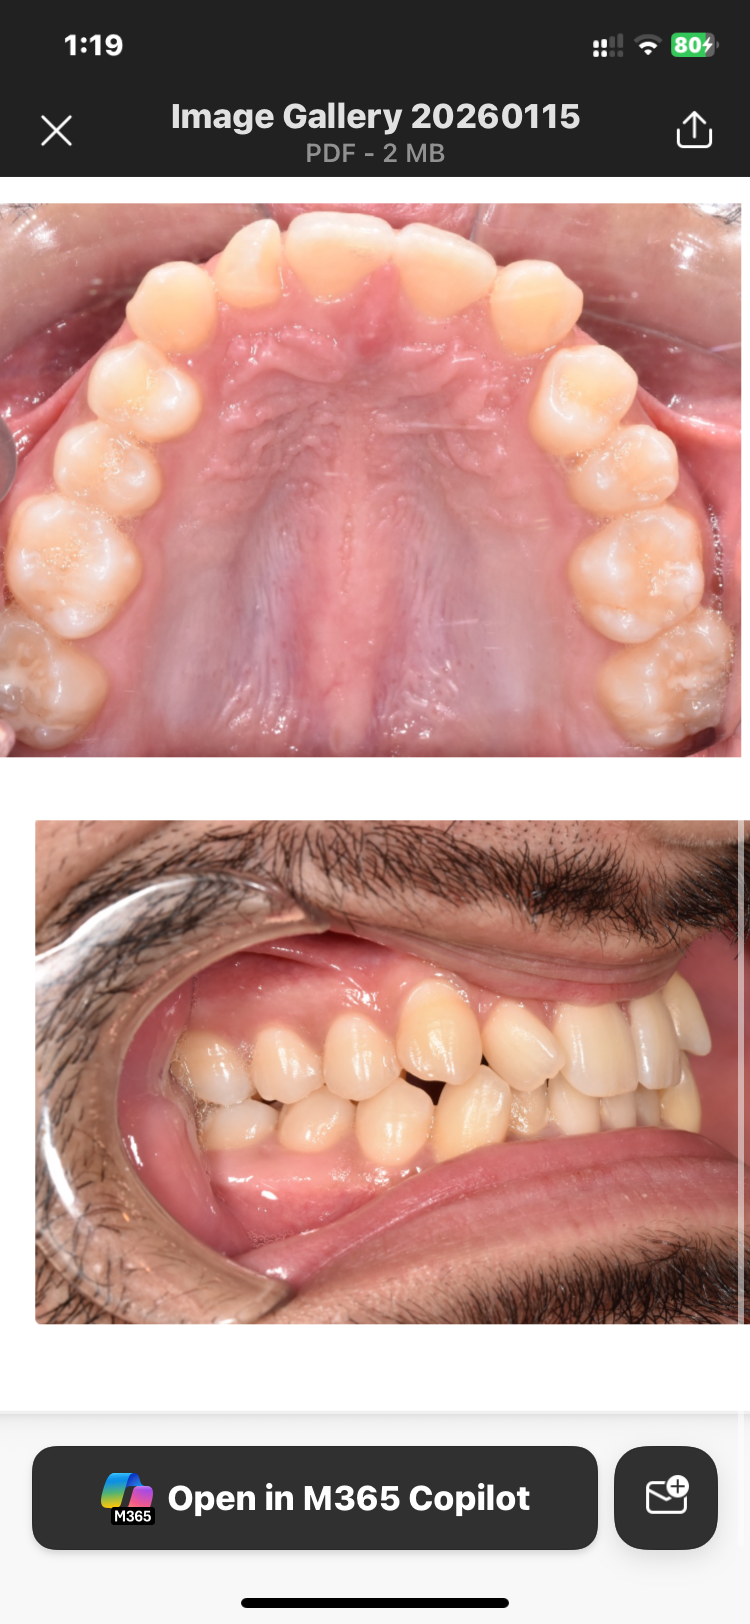

They want me to get elastic braces and see what we do maybe move with invisalign or whatever is best needed for my treatment. If you have decent knowledge in this field respond and give advice for treatment. pls don’t message if u don’t know anything low iq type move

If they are moving my jaw back I would know and not continue with him he wanted to do extractions but I told him I wanted to avoid recession so we are doing regular braces.